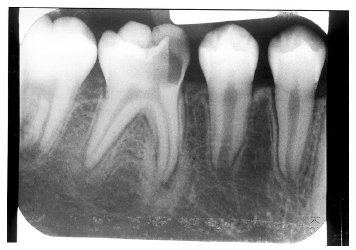

condensing osteitis= Focal sclerosing osteomyelitis

通常在下顎後牙

慢性刺激 通持死牙/pulp necrosis

RO + thickened PDL space